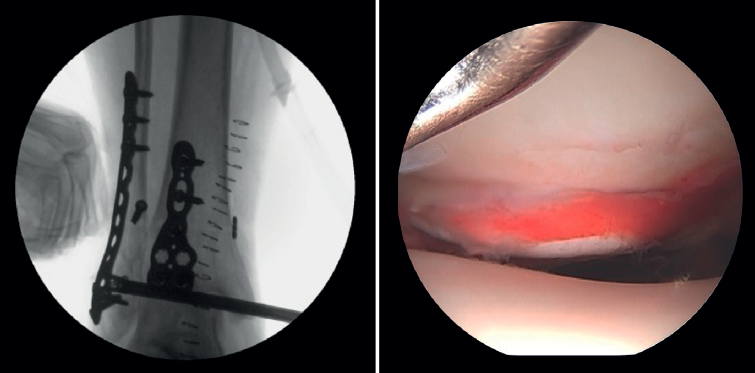

Placement in the operating room

First, we adopt the posterior approach, if required by the fracture involved, and, after reducing the posterior malleolus, we place the patient in the supine position with a pad under the buttock. The ankle should be positioned at the edge of the operating table, which will allow free ankle flexion and extension, facilitating handling during arthroscopy. Ischemia and water aspiration and irrigation systems are placed on the same side as the fracture (but this may vary according to the technical peculiarities of each hospital). The arthroscopy tower and fluoroscope monitor are placed close to the patient's head and, on the contralateral side, we place the C-arm at the bottom to optimize visualization and arthroscopic and radiological access, allowing simultaneous use(7)(Figure 1 and Table 1).

- Assessment of reduction of the posterior malleolus: arthroscopy can be used to verify reduction of the posterior malleolus(5)(Figure 2).